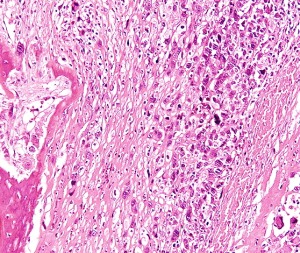

Knochenkrebs: Überlistung nach dem Troja-Vorbild möglich (Foto: Wikimedia) |